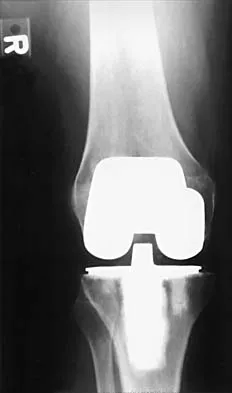

A 42-year-old man sustained the periprosthetic fracture shown in Figures 19a and 19b. The femoral component is well fixed. What is the next most appropriate step in management?

Explanation

The patient has a periprosthetic fracture below the femoral stem. The component is porous coated and well fixed. Open reduction and internal fixation, leaving the stem in place, can be performed when bone quality is good. Plating with or without allograft struts and supplemental cerclage fixation generally is acceptable. If the component is loose, revision to a longer device is recommended with appropriate stabilization of the fracture using the aforementioned methods. If bone loss has occurred, allograft supplementation or a tumor prosthesis may be indicated. Fractures located well below the stem tip can be treated without regard for the prosthesis. Closed reduction and bracing is not associated with good results for periprosthetic femoral fractures. Retrograde intramedullary nailing is not appropriate for this fracture. Duncan CP, Masri BA: Fractures of the femur after hip replacement. Instr Course Lect 1995;44:293-304.